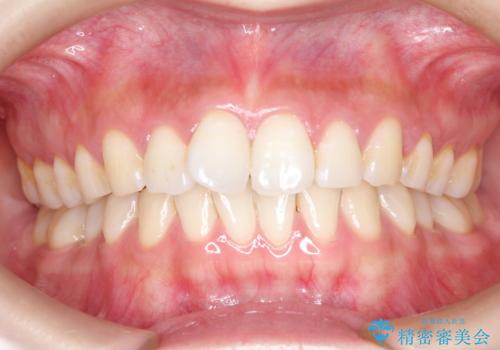

長い間コンプレックスだった前歯のすき間! 短期間終了。部分矯正症例 (インビザライン矯正)